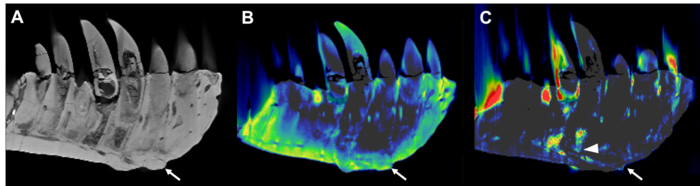

Charlie Hamm, M.D., a radiologist at Charité University Hospital in Berlin, and his colleagues recently had an opportunity to investigate a portion of the Tristan Otto’s lower left jaw. While previous fossil studies have mostly relied on invasive sampling and analysis, Dr. Hamm and colleagues used a noninvasive approach with a clinical CT scanner and a technique called dual-energy computed tomography (DECT). DECT deploys X-rays at two different energy levels to provide information about tissue composition and disease processes not possible with single-energy CT.

The CT technique enabled the researchers to overcome the difficulties of scanning a large portion of Tristan Otto’s lower jaw called the left dentary. The piece’s high density was particularly challenging, as CT imaging quality is known to suffer from artifacts, or misrepresentations of tissue structures, when looking at very dense objects.

On visual inspection and CT imaging, the left dentary showed thickening and a mass on its surface that extended to the root of one of the teeth. DECT detected a significant accumulation of the element fluorine in the mass, a finding associated with areas of decreased bone density. The mass and fluorine accumulation supported the diagnosis of tumefactive osteomyelitis, an infection of the bone.